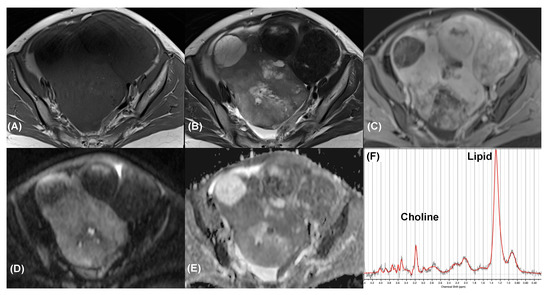

| Case | Histopathology | Malignancy | O-RADS | DWI | MRS |

|---|---|---|---|---|---|

| 1 | Serous cystadenocarcinoma | Yes | 5 | TP | FN |

| 2 | Serous cystadenocarcinoma | Yes | 5 | TP | FN |

| 3 | Metastatic carcinosarcoma | Yes | 5 | TP | FN |

| 4 | Clear cell carcinoma | Yes | 5 | FN | TP * |

| 5 | Clear cell carcinoma | Yes | 4 | FN | TP * |

| 6 | Clear cell carcinoma | Yes | 4 | FN | TP * |

| 7 | Endometrioid carcinoma | Yes | 4 | FN | TP * |

| 8 | Endometrioid carcinoma | Yes | 4 | TP | FN |

| 9 | Endometrioid carcinoma | Yes | 4 | TP | TP |

| 10 | Endometrioid carcinoma | Yes | 4 | TP | TP |

| 11 | Serous cystadenocarcinoma | Yes | 4 | TP | TP |

| 12 | Serous cystadenocarcinoma | Yes | 4 | TP | FN |